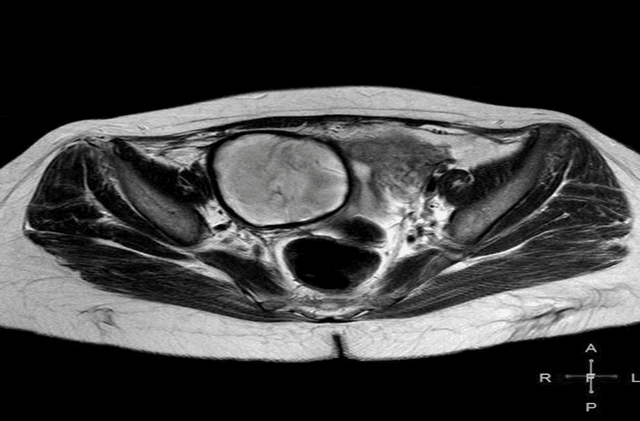

Background, For the purpose of determining the appropriate course of therapy to maintain fertility, a correct diagnosis of ovarian cysts is crucial. Objective, To contrast the results of magnetic resonance imaging and ultrasonography in individuals with ovarian cysts . Methods: research was carried out in the radiology division of Al-Hilla General Teaching hospital and Marjan Teaching Hospital in province Babil in the period of November 2023 and march 2024, Seventy-five Following a physical and ultrasonography examination, the female patient was assessed using magnetic resonance imaging. Women in the over-18 age group exhibit a range of symptoms, such as irregular menstruation, abdominal pain, sensoria, and menorrhagia. Results: Adnexal lesions on US imaging included chocolate cysts (14.6%), dermoid cysts (13.8%), hemorrhagic cysts (HC) (11.6%), simple cysts (32.4%), complicated cysts (21.2%), and multilocular cysts (MC) (6.4%).Simple cysts (SC) made up 29%, complex cysts (6.9%), dermoid cysts (10.9%), chocolate cysts (19.1%), hemorrhagic cysts (HC) 11.3%, multilocular cysts (6.8%), and malignant cysts (MC) 16% of the adnexal lesions on MRI. The USG results show 100% sensitivity, 78.3% specificity, and 89.3% accuracy when compared to the MRI results. Conclusions: Magnetic resonance imaging, which is quite accurate in determining the mass's origin and characterizing its tissue content, may be beneficial in further evaluating monographically vague ovarian cysts with solid or complicated content